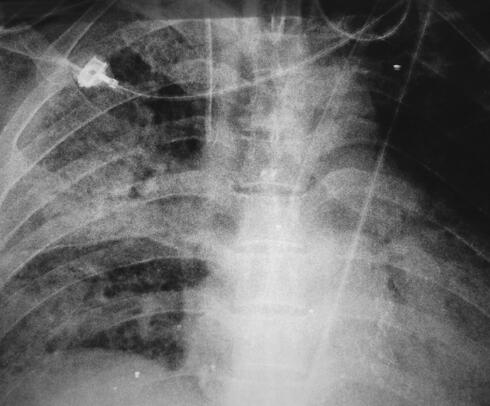

诊治经过:入室后给予吸氧监护,抽血培养,每小时1次,共抽3次血培养后开始经验性抗感染治疗。选用万古霉素+阿米卡星联合治疗,以及其他输液支持对症治疗。患者体温、症状、氧合以及一般情况仍无好转,第3天将阿米卡星换为亚胺培南-西司他汀钠。第4天因患者储氧面罩吸氧时氧合在90%左右,给予患者经口气管插管接呼吸机辅助通气,氧浓度50%+PEEP 10cmH2O的条件下可维持指氧93%左右。多次经气管插管吸痰送检细菌、真菌、结核涂片、培养均阴性,5次血培养结果均阴性,抽血查免疫全套、肿瘤标志物全套均阴性,复查床旁胸片提示双肺多发渗出(图3)。

图3 胸部X线片示双肺多发渗出